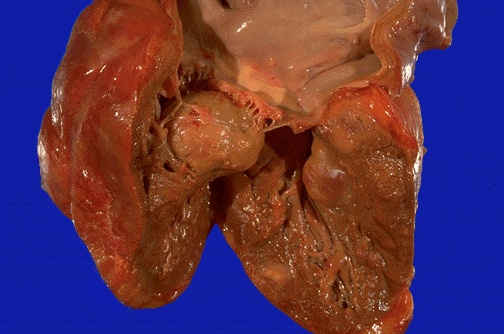

| Just beneath the mitral valve in the left ventricular chamber can be seen a large tumor mass extending from the endocardial surface. A metastatic carcinoma could have this appearance. (Actually, this turned out to be a "chloroma" or a mass of leukemic cells in a patient with myelogenous leukemia). |